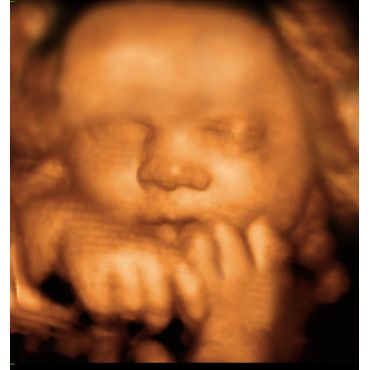

Three-dimensional (3D) Ultrasound is one of this decade's high tech marvels. I produces amazing life-like pictures of your unborn baby. Compared to traditional 2D Ultrasound, 3D shows incredible details and clarity. Real-time, also called 4D Ultrasound, allows you to view your baby's movements inside your womb. The best results are obtained by having your 3D Ultrasound between 20-35 weeks of your pregnancy.

Benefits of 3D/4D Ultrasound allows expectant parets, siblings and family members to have an opportunity to witness the miracle of life and begin instantly bonding with the unborn baby. Parents cherish this unforgettable experience because it amplifies the beauty of pregnancy and creates heightened excitement around the birth of the baby. Research shows that mothers who experience 3D Ultrasound feel more connected to their unborn babies. They also tend to take medical advice more seriously, which in turn improves healthy outcomes for both mother and baby.